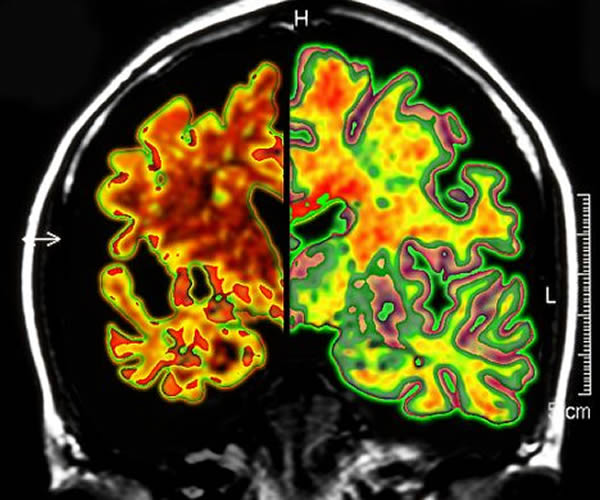

这张为痴呆综合症令大脑萎缩的图片